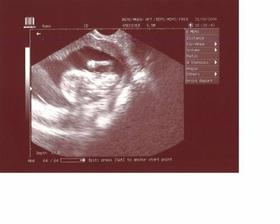

2.5. -Já jsem tak šikovnej ... jsem akorát, jsem živoučký, až mě nemohli ani vyfotit 🙂 a nožičky jsem měl zase křížem, takže co jsem, se neptejte 😀 ale pan doktor mě chválil... i maminku .. přibrala zatím krásných 4,5 kila